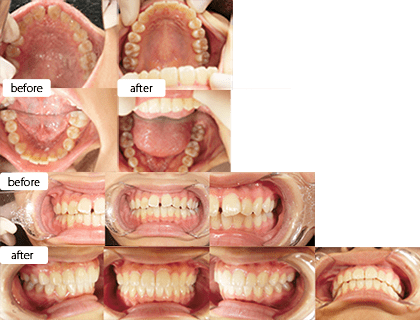

治療方法 上下床矯正装置+インビザライン

(親知らず抜歯)治療の説明 主訴: 右上1と右下1が出ている、叢生 年齢 23歳 ![]()

治療費用 877,800円(税込)

(インビザライン767,800円 床矯正2装置110,000円)治療期間 3年1ヶ月 通院回数 18回 治療の副作用(リスク) 咬合痛、歯根吸収、歯根露出が生じる可能性があります。 歯科医師からのコメント 上下で拡大床装置ありで期間は3年ですが、右上1番の唇側傾斜が改善、しっかり噛めるようになっています。 本人許可 症例写真としてのHPなどへの掲載許可を得ています。